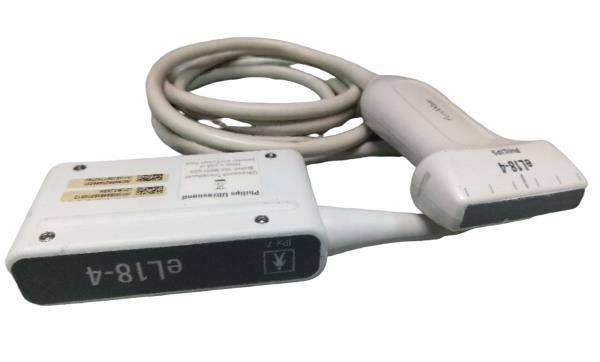

Designed with portability and functionality in mind, the New Portable Notebook Digital Laptop Machine offers superior performance without compromising on ease of use. Its compact size allows for easy transport and setup, while the digital laptop interface ensures that users can quickly access and utilize the scanner's capabilities. The inclusion of a convex probe and 3D imaging further enhances the diagnostic accuracy, providing clearer and more detailed images than ever before.

In addition to its user-friendly design, the New Portable Notebook Digital Laptop Machine provides high-resolution imaging that is crucial for accurate diagnostics. The 3D imaging capability allows for more comprehensive assessments of anatomical structures, leading to better treatment planning and patient management. Whether used for routine check-ups or complex medical evaluations, this ultrasound scanner delivers reliable and precise results.